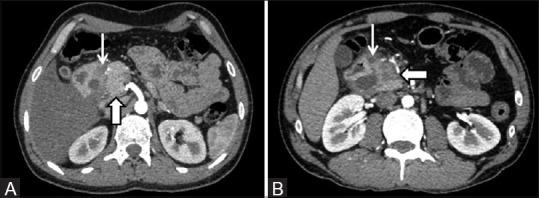

All patients were young to middle-aged men (100%) with history of alcohol abuse (93.9%) and/or smoking (42.4%), who presented either with acute or gradually worsening abdominal pain (90.9%). Pancreatic enzymes and serum tumor markers remained normal or were mildly/transiently elevated. Cystic variant was detected in 57.6% (solid in 42.4%); the disease remained confined to the groove/duodenum (pure form) in 45.4%. Medial duodenal wall thickening with increased enhancement was seen in 87.87 and 81.81%, respectively, and duodenal/paraduodenal cysts were seen in 78.78%. Pancreatic calcifications and biliary stricture were seen 27.3% patients. Peripancreatic arteries were neither infiltrated nor encased.

PP has a discrete predilection for middle-aged men with history of longstanding alcohol abuse and/or smoking. Distinguishing imaging findings include thickening of the pancreatic side of duodenum exhibiting increased enhancement with intramural/paraduodenal cysts. This may be accompanied by plate-like scar tissue in the groove region, which may simulate groove pancreatic carcinoma. However, as opposed to carcinoma, the peripancreatic arteries are neither infiltrated nor encased, rather are medially displaced.

所有患者均为中青年男性(100%),有酗酒史(93.9%)和/或吸烟史(42.4%),表现为急性或逐渐加重的腹痛(90.9%)。胰腺酶和血清肿瘤标志物保持正常或轻度/短暂升高。57.6%检测为囊性变(42.4%为实性);45.4%的疾病局限于沟/十二指肠(纯形式)。分别有87.87%和81.81%的患者出现十二指肠内侧壁增厚且强化增加,78.78%的患者出现十二指肠/十二指肠旁囊肿。27.3%的患者出现胰腺钙化和胆管狭窄。胰周动脉未受侵犯也未被包绕。

PP对有长期酗酒和/或吸烟史的中年男性有明显偏好。具有鉴别意义的影像学表现包括十二指肠胰腺侧增厚,壁内/十二指肠旁囊肿强化增加。这可能伴有沟区的板状瘢痕组织,可能类似沟部胰腺癌。然而,与癌不同的是,胰周动脉未受侵犯也未被包绕,而是向内侧移位。